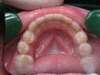

Le traitement orthodontique doit se terminer par une phase de contention : période qui permet de consolider les résultats obtenus grâce au traitement orthodontique. Elle est réalisée le plus souvent par un fil métallique collé sur la face linguale des dents.